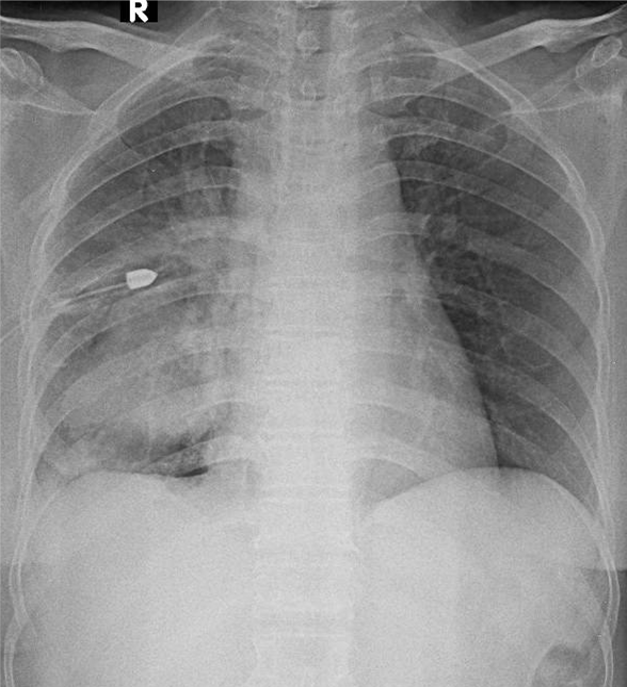

1-Thâm nhiễm phế nang lan tỏa phổi (P) => Viêm phổi 2-Khối mờ đồng nhất thùy dưới phổi (P) => TD u phổi 3-Tràn dịch màng phổi (P) 4-Đang dẩn lưu màng phổi (P)